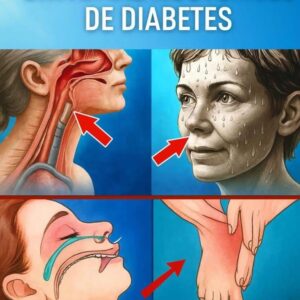

Cuales son los sintomas de la diabetes

Niveles (en ayunas): Lo normal es entre 80 y 115 mg/dl. Si tienes más de 115 mg/dl es alta (hiperglucemia) y menos de 70 mg/dl es baja…